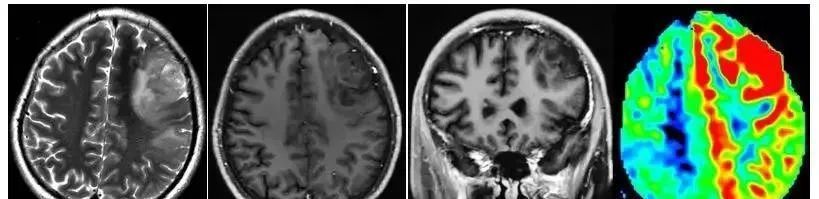

3D ASL能准确评价胶质瘤的微循环灌注信息,因而能反映肿瘤病变的新生血管形成,据此可以更准确的评价胶质瘤分级。有些胶质瘤病变尽管在常规增强无强化,但在3D ASL上表现为明显的高灌注,病理证实为高级别的胶质瘤。低级别的胶质瘤在3D ASL上表现为低灌注。